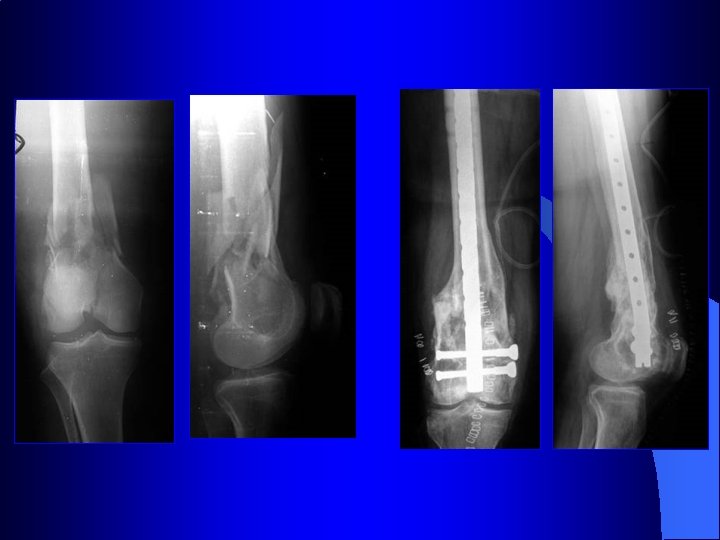

Indication des plaques : les fractures métaphysaires

Indication des plaques : les fractures métaphysaires Manuel AO

Synthèse des fractures des malléoles

Traitement des fractures malléolaires 54 ans Bon résultat à 61